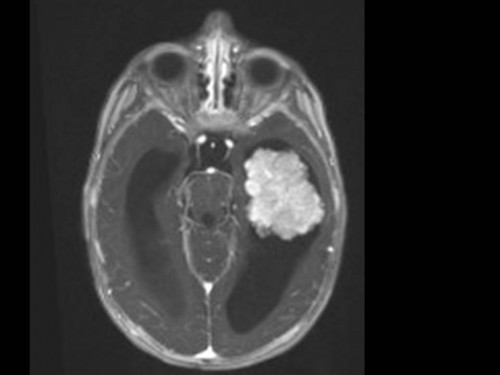

10 Monate altes Mädchen. Der Kinderarzt stellt fest, dass das kleine Mädchen einen recht großen Kopfumfang hat, nicht mit den Augen fixiert und anscheinend auch nicht richtig sehen kann. Damit bestätigt er die größten Befürchtungen der Eltern, denen in den letzten Wochen aufgefallen war, dass ihre Tochter nach keinem Spielzeug mehr greift und sie nur dann anlächelt, wenn sie zu ihr sprechen.

Bildgebung - MRT